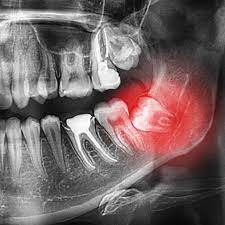

If you're wondering, “Do I need a panoramic X-ray for my dental checkup?”, you're not alone. Many patients are unsure when and why dentists recommend this type of imaging. A panoramic dental X-ray is a special type of scan that captures a complete view of your upper and lower jaw, all teeth, temporomandibular joints (TMJ), and surrounding bones in a single image. While it's not required for every routine dental visit, it plays an important role in diagnosing conditions that can’t be seen with traditional Dental Panoramic X-Ray In Dubai. Your dentist may recommend it based on your dental history, symptoms, or treatment planning needs.

- Suspected wisdom teeth issues

- Detecting bone loss, cysts, or tumors

- Monitoring impacted or missing teeth

If your dentist notices signs of underlying issues—such as swelling, asymmetry, or crowding—they may use a panoramic image to investigate further. It's a tool that helps uncover conditions that don’t always cause visible symptoms.